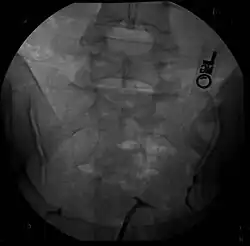

| Hysterosalpingography of a T-shaped uterus. | |

Women are often diagnosed with this condition after several failed pregnancies, proceeded by exploratory diagnostic procedures, such as magnetic resonance, sonography, and particularly hysterosalpingography.[6][7][8] In such studies, a widening of the interstitial and isthmus of uterine tube is observed, as well as constrictions or narrowing of the uterus as a whole, especially the lower and lateral portions, hence the "t" denomination. The uterus might be simultaneously reduced in volume, and other abnormalities might be concomitantly present.[9]